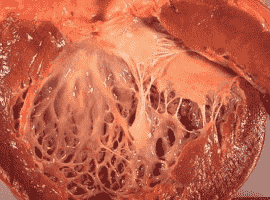

Citation: Stephanie P, Coutinho T, et al. A Clinical Case on Coronary Artery Disease. Clin Image Case Rep J. 2021; 3(7): 178.